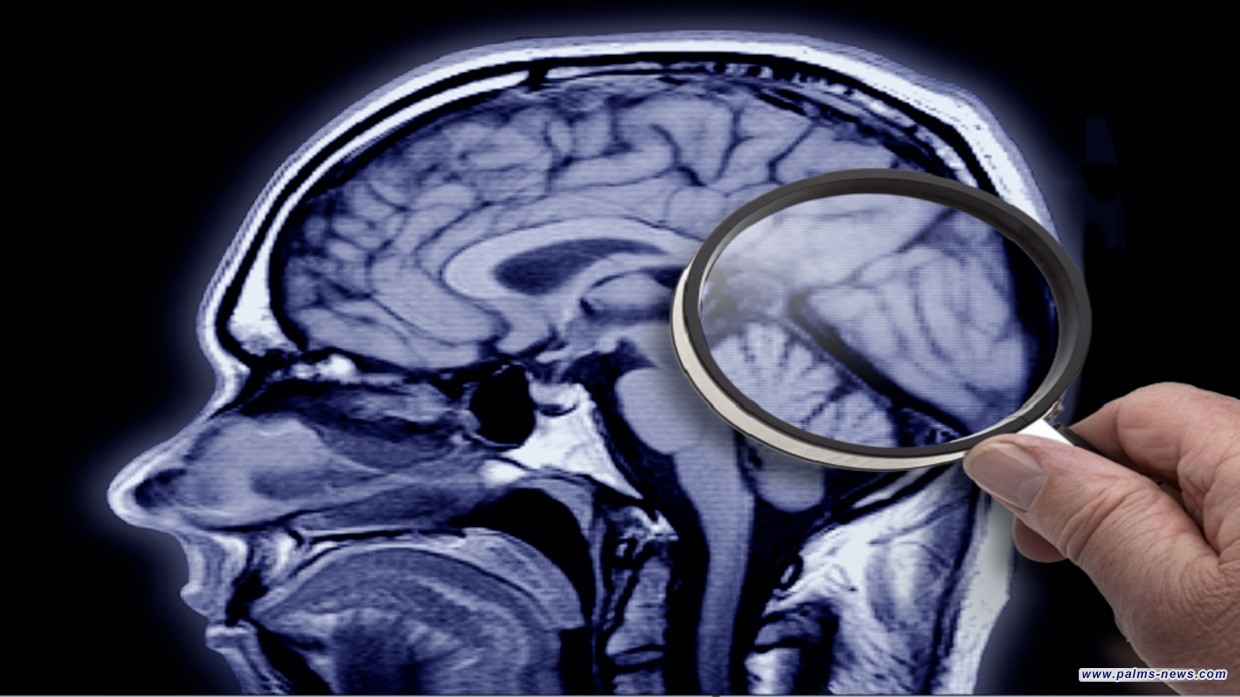

اكتشاف رائد قد يحمل مفتاح علاج ألزهايمر قبل عقود من ظهور الأعراض

أظهر فريق من العلماء، لأول مرة، أن مرض ألزهايمر يتطور عبر مرحلتين رئيسيتين.

وفي الدراسة، التي نشرها باحثون من جامعة واشنطن ومعهد ألين لعلوم الدماغ في مجلة Nature Neuroscience، حلل العلماء أكثر من 3.4 مليون خلية فردية من أدمغة 84 متبرعا متوفى، من منطقة تُعرف بالتلفيف الصدغي الأوسط، والتي تلعب دورا مهما في معالجة اللغة والذاكرة.

وباستخدام خوارزمية متقدمة، قارن فريق البحث الخلايا غير الصحية بتلك الموجودة في دراسات سابقة عن الأفراد الأصحاء، ليكتشفوا مرحلتين رئيسيتين لمرض ألزهايمر، حيث تحدث المرحلة الأولى بهدوء، مع تغييرات دقيقة في الخلايا التي تحمي الخلايا العصبية وفقدان طفيف للخلايا (يحدث ذلك على مدى فترة طويلة، دون أن يؤثر على الذاكرة).

أما المرحلة الثانية فهي سريعة وشرسة، تتميز بتكوين سريع لبقع بروتينية ضخمة تؤثر على أنسجة الدماغ السليمة، ما يؤدي إلى فقدان الذاكرة والإدراك.

وقال الدكتور ريتشارد هودز، مدير معهد الشيخوخة التابع للمعاهد الوطنية الأمريكية للصحة، الذي مول الدراسة: "هذه النتائج تعيد تشكيل فهمنا لكيفية تأثير مرض ألزهايمر على الدماغ، وستساعد في توجيه تطوير علاجات جديدة لهذا الاضطراب المدمر".

وأضاف: "أصبحنا قادرين على اكتشاف التغيرات المبكرة، ما يمنحنا لمحة عما يحدث في الدماغ خلال المراحل الأولى للمرض".

وأشار الدكتور جون ناي، مدير معهد BRAIN، إلى أن المعرفة الجديدة التي توفرها هذه الدراسة قد تساعد العلماء ومطوري الأدوية في جميع أنحاء العالم على تطوير تشخيصات وعلاجات مستهدفة لمراحل محددة من مرض ألزهايمر وأشكال الخرف الأخرى.